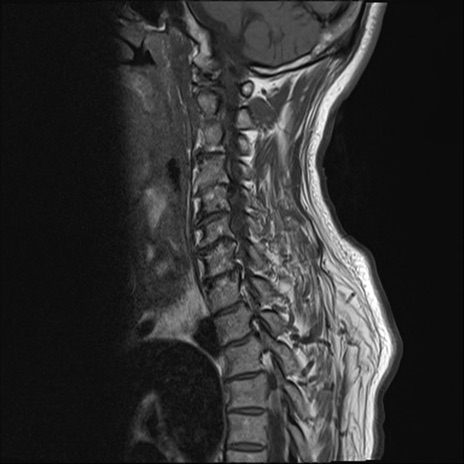

【整形】TIPS症例7 頚椎MRI T1WI(矢状断像)

頚椎MRI

T2WI(矢状断像)